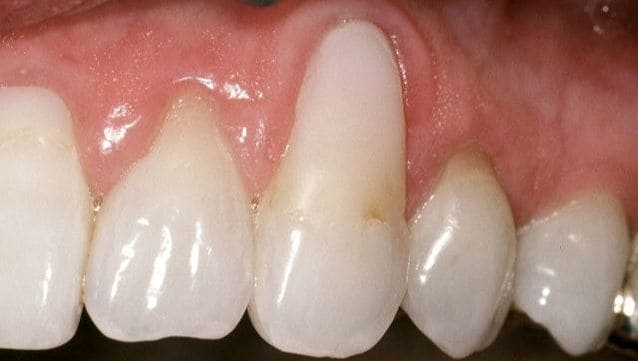

Before

After